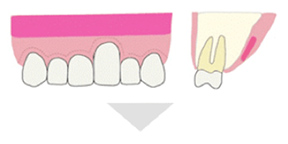

特徴5:治療後、美しい口元に改善する「歯肉移植術」

歯周病が進行すると、顎の骨が徐々に吸収されるとともに、炎症によって歯肉が腫れ上がります。骨の吸収が進めば歯肉は下がり、歯根が露出して歯が長く見える状態になりますが、炎症による腫れによって外見上はその変化が分かりにくくなります。治療によって炎症が改善されると、腫れが引き、隠れていた歯の部分が見えるようになるため、結果として「歯が長くなった」ように見えるのです。

当院では、治療後に審美的な見た目が気になる場合の改善策として「歯肉移植術」を実施しています。これは上顎の健康な歯肉の一部を採取し、見た目の改善が必要な部位に移植する方法で、歯肉ラインの回復と審美性の向上を目的としています。

Step1 歯肉の採取:上顎の奥歯の内側から移植する歯肉を採取します。

Step2 歯肉の移植:移植する箇所の歯茎を切開し、その中に採取した歯肉を入れます。

Step3 歯茎の縫合

歯肉を採取するために切開した歯茎は2週間程度でもとどおりになり、移植された歯茎はおよそ1ヶ月程度で傷跡がなくなり、周囲の歯茎と区別がつかない自然な状態になります。